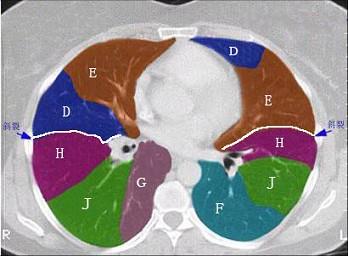

问题 结合肺段模式肺动脉干与右肺动脉层面肺动脉干与右肺动脉层面(见图), 心室层面(见图), 主动脉弓层面(见图), 左右心房层面(见图),选出左肺上叶的组成 ( )

选项 A、A+B+C+D+E B、A+B+C+D+E+F C、A+B+C D、A+B+C+D E、A+B

答案 A